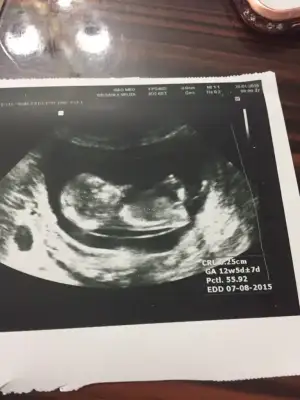

Kesin kiz diyorumMerhaba hamişler bende 12+2inci haftamdayım bugün ikili test için hastaneye gittim vee çıkıntınında belli olduğu güzel bi foto yakaladık yorumlarınız çok sevinirim canlar

Bence kızMerhaba hamişler bende 12+2inci haftamdayım bugün ikili test için hastaneye gittim vee çıkıntınında belli olduğu güzel bi foto yakaladık yorumlarınız çok sevinirim canlar